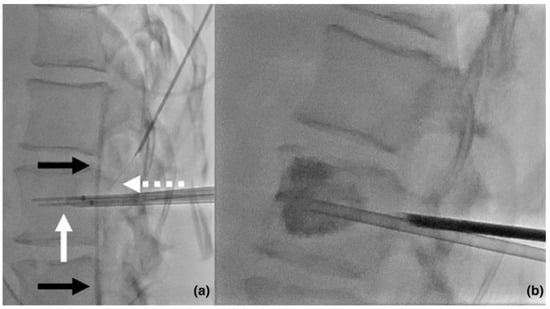

- Faiella, E.; Pileri, M.; Santucci, D.; Pusceddu, C.; Fior, D.; Riva, F.; Tagliaferri, C.; Moramarco, L.P.; Zobel, B.B.; Grasso, R.F. Transoral percutaneous radiofrequency ablation with a steerable needle and cementoplasty under CBCT and infrared augmented reality navigation system guidance for the treatment of a C1 solitary plasmacytoma: A case report. Radiol. Case Rep. 2024, 19, 890–894. [Google Scholar] [CrossRef]